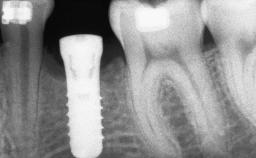

A 47-year-old woman who had suffered from aggressive periodontitis requiring a number of periodontal interventions over more than 10 years was referred by her general dental practitioner and periodontologist for bone augmentation and implant therapy. Her failing dentition had already been scheduled for extraction. The patient expressed a desire for implant-supported fixed restorations and esthetic improvement of her lower face. She had agreed to consult with a maxillofacial surgeon after the referring dentist had suggested bone augmentation. An initial examination by the maxillofacial surgeon revealed mobility of all residual teeth in a patient who was very unhappy with the function of her removable partial dentures. Due to periodontally migrated flaring teeth and loss of occlusal support, the vertical dimension of occlusion was dramatically reduced. The patient was displeased with her lower face because of deepened nasolabial, commissural, and supramental folds.

# of Implants 14

Type of Implants Two-Piece

Bone Augmentation Horizontal|Sinus Floor Elevation|Staged|Vertical